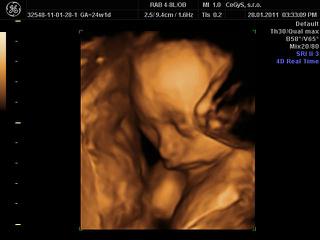

ahojte, my sme dnes boli na 3D, takže sme plní zážitkov 😀

no, princeznička je to na 100 percent 😎 😎 😎 veľmi sa tešíme. Na začiatku sa nám ukazovala pekne, potom už sme ju asi otravovali tak sa zabárala noštekom do placenty a nechcela sa ukázať.. ale máme asi 10 videosekvencií a 10 fotiek takže super!!!!

@alena24 no spolupracovala prvych 10 minut potom sme ju len tahali zo strsny na stranu, opica jedna, ale stihli sme to na zaciatku ponahravat, sme sa poucili z morf.uzv, tam sa nam tiez schovavala!!! Ano aj nas meral, zodpovedame presne tt, cize 24,4 tt a vazime 670 g. Aj nam ukazoval nejaky graf k tomu a ideme pekne stredom, co je priemer tak ako ma byt.